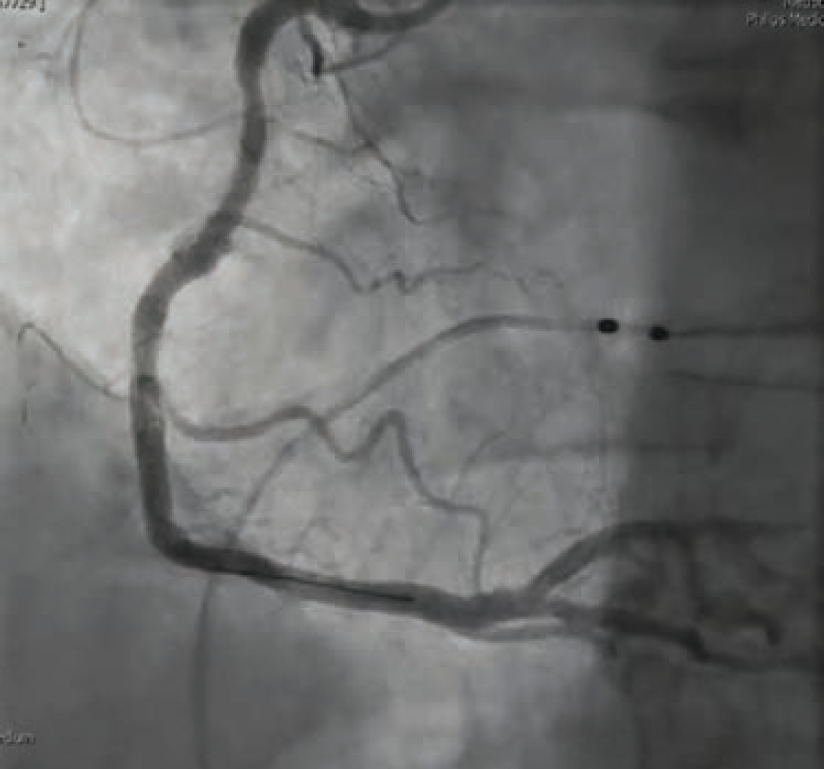

For our patient’s CFT analysis, a coronary angiogram was performed and regarding epicardial disease, demonstrated unchanged results from the previous angiogram (Figure 1). Next, we confirmed a negative invasive functional test for CMD (Figure 2). However, because the patient developed chest pain and demonstrated ST changes on electrocardiogram during ACh provocative testing, without epicardial spasm, her assessment was positive for microvascular vasospastic angina.